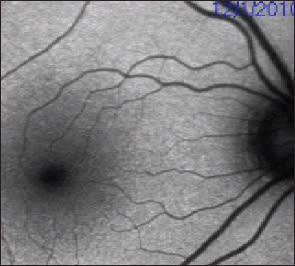

2. Proliferative DR: FA vs. OCT

Most Optimal Technique

Advantages: See areas of NV and choroidal nonperfusion; used to target laser therapy.

Limitations: Longer test; invasive; requires more patient cooperation; may not see anti-VEGF response as clearly.

Alternative Technique

Advantages: Quantification of diabetic macular edema.

Limitations: Cannot visualize NV or non-perfusion; only captures macula, not the periphery.